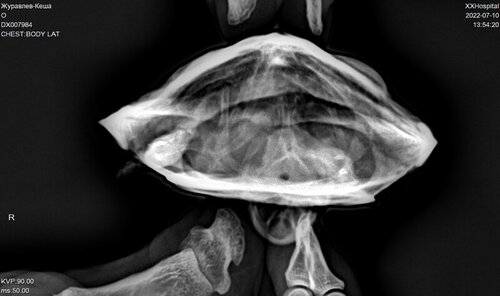

DX007984_1.JPG

DX007984_2.JPG

DX007984_3.JPG

Исправили температурный режим, УФ лампу заказали скоро должна прийти. В телеграмканале не отвечают что делать дальше. Написали про газы в целоме, что делать с ними?